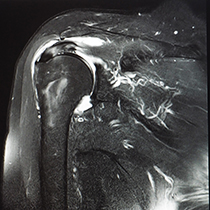

RMN umar

RMN-ul de umar este o investigatie non-iradianta si nedureroasa, ce ofera imagini clare pentru diagnosticarea leziunilor umarului.